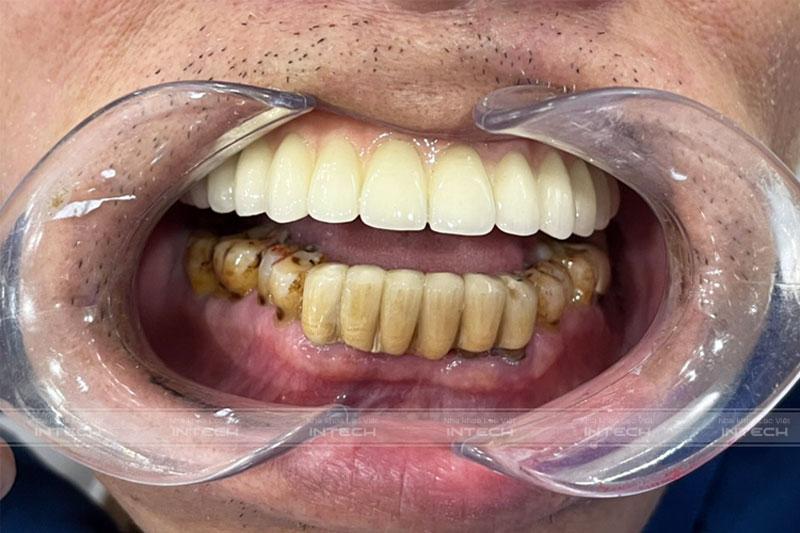

Kết quả sau khi lắp hàm cố định của chú Phương, bác sĩ thiết kế màu sắc, dáng răng tương đồng với răng thậtKết quả sau khi lắp hàm cố định của chú Phương, bác sĩ thiết kế màu sắc, dáng răng tương đồng với răng thật

Sau 3 tháng chờ trụ Implant tích hợp, chú Phương cuối cùng cũng được lắp răng sứ cố định và hoàn tất quá trình điều trị. Hiện tại, chú đã sở hữu hàm răng chắc chắn, thẩm mỹ như răng thật, nhờ đó ăn uống cũng cảm thấy ngon miệng hơn và sức khỏe được cải thiện.

Dưới đây là hình ảnh chú Phương trong buổi lắp răng tại Nha khoa Lạc Việt Intech.

Chú Phương cảm thấy rất hạnh phúc với hàm răng hiện tạiChú Phương cảm thấy rất hạnh phúc với hàm răng hiện tại

“Lúc chưa làm răng thì hai bên má hóp lại, khiến việc giao tiếp của chú mất tự nhiên. Sau khi làm răng xong thì cảm thấy má đầy lên, da dẻ căng hơn nên cảm thấy mình trẻ ra vài tuổi”. - Chú Phương tâm sự.

“Chú cảm thấy rất hài lòng với hàm răng hiện tại. Cảm ơn đội ngũ bác sĩ và nhân viên tại Nha khoa Lạc Việt Intech đã rất tận tình và giúp đỡ tôi sở hữu một hàm răng đẹp, bền chắc như ý”.